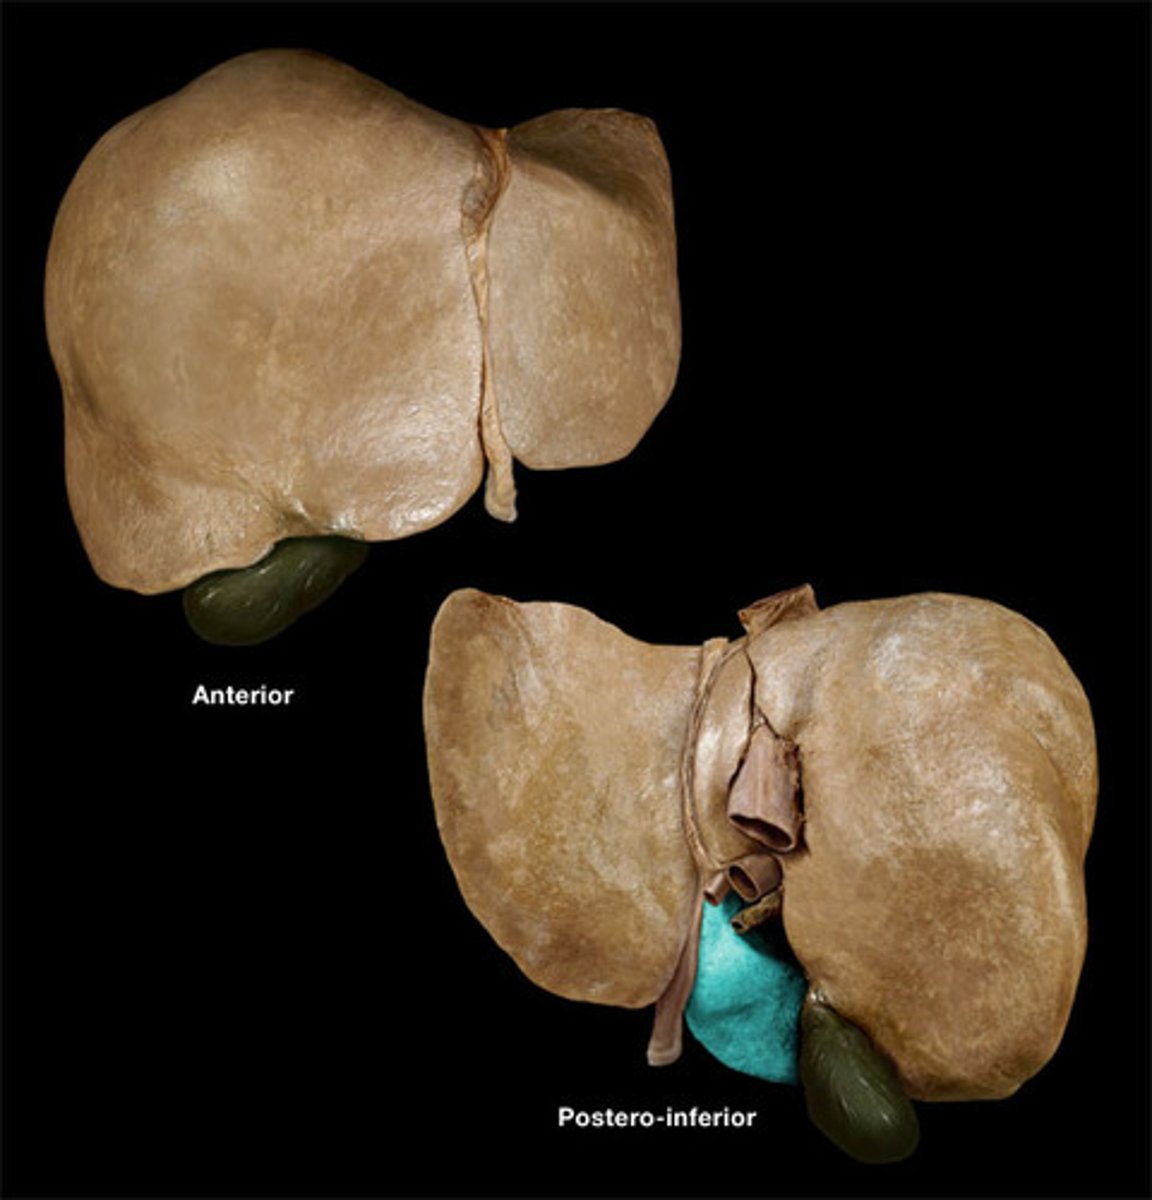

porta hepatis

where the blood and lymph vessels, bile ducts, and nerves enter and leave the liver

hepatic artery proper

common bile duct

common hepatic duct

cystic duct

hepatic portal vein

gallbladder